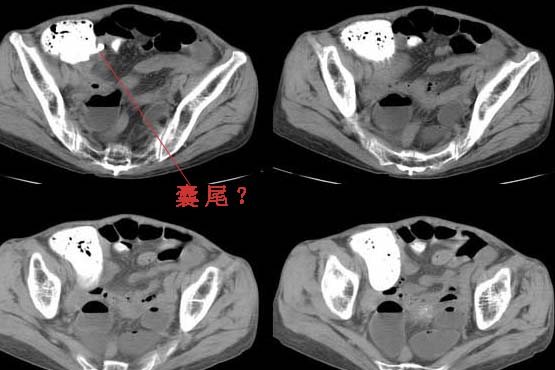

次日中午外科开下腹及盆腔ct,上次ct至次日中午患者一直没进食,患者家属拒绝做全肠道准备,图像如下:

补充一下患者有右下腹的压痛!大家分析的很有道理,请大家继续讨论。

我的病例人气真的很低,不过不要紧,我来公布手术的结果吧,看了结果请大家继续做总结性发言。这个病人做完第二个ct后就手术了,术中发现乙状结肠过长,阑尾短粗并且已穿孔,过长的乙状结肠包裹了穿孔的阑尾致使乙状结肠以上的降、横、升结肠扩张,壁如薄纸(回盲瓣是单向的,乙状结肠又粘连了,所以气体只能积在此区域,直肠呈闭塞状态)。回头看这个图像,阑尾是很清楚的充填了造影剂,可是阑尾周围真的是很毛糙。我只说这么多请大家继续做总结性发言!

下图是回盲部局部解剖:

阑尾是人类的一种退化器官(食草动物的阑尾很发达),长约7-9厘米,直径约0.5厘米。本例显然已经非常粗短,穿孔的征象也比较确切,肠内容物漏出并弥散在阑尾周围。冗长的乙状结肠jiajie 老师已经用图片分析的十分透彻,我只是用图片指示一下其与阑尾及盲肠末端包裹、粘连的情况。如有不对的地方,请各位老师指正,先行感谢了!